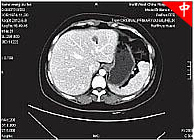

根据患者病情南京太乙堂中医院专家为患者制定了“扶正祛邪·抗癌消瘤体系”的治疗方案,先用“扶正祛邪·抗癌消瘤体系”治疗两个疗程,然后在根据患者恢 复将情况进行下一步治疗方案。在接受“扶正祛邪·抗癌消瘤体系”的同时,患者积极进行心理辅导、营养支持、情绪调节。两个疗程的中医治疗结束后,CT片 显示患者的病情有了明显的好转,人也胖了起来,食欲增加了,这给张女士带来了很大信心。张女士主动要求再次进行了一个疗程的加强治疗。通过三个疗程的治 疗,身体状况良好,医生建议患者回家调养。